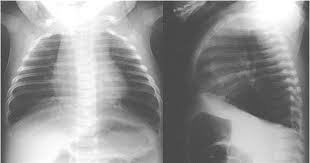

- X-quang phổi: cho thấy tim to cùng nhĩ phải và hai thất giãn, cung động mạch phổi nổi và dấu hiệu mạch máu phổi đậm.